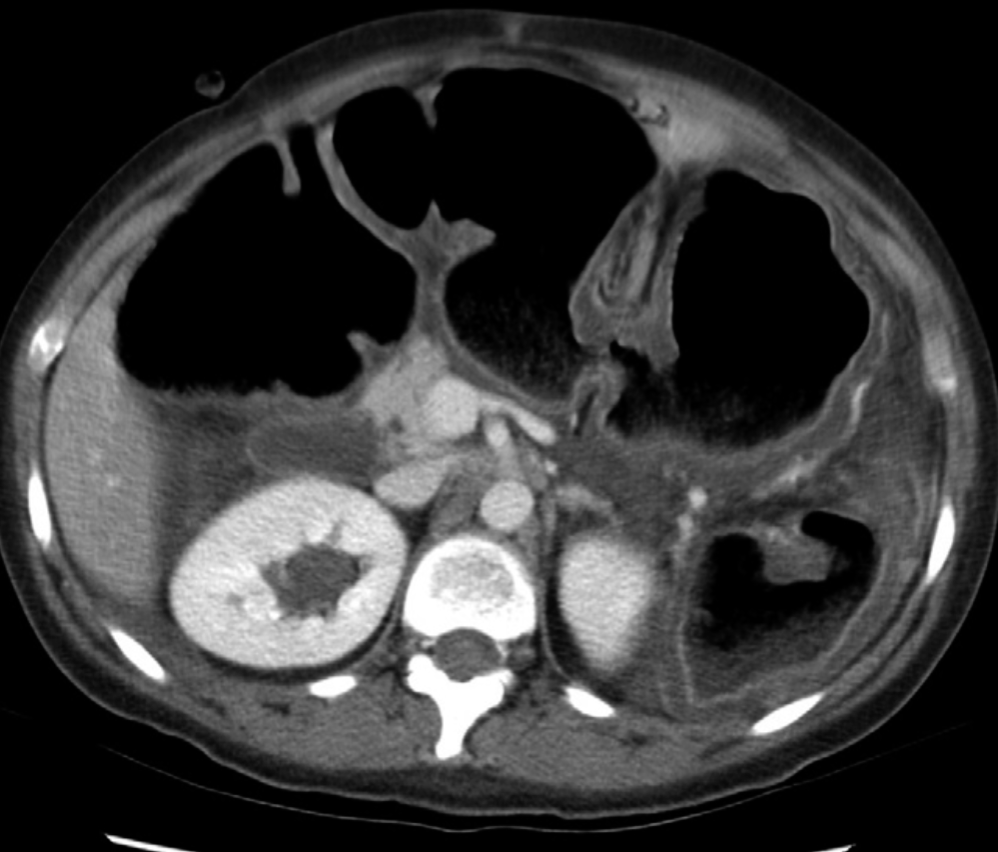

- The dilation is typically greater than 6 cm in the transverse colon, but the entire colon can be affected.